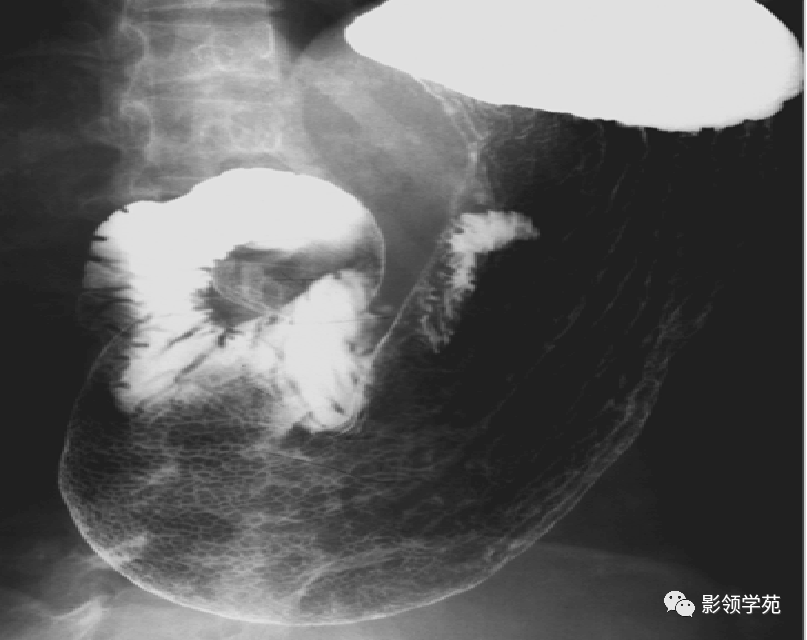

钡餐片子正常图片,

钡餐双重造影

消化道疾病影像诊断与鉴别